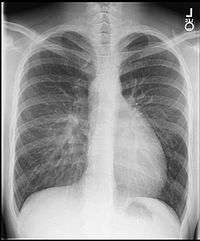

On chest X-ray, transposition of the great vessels typically shows a cardio-mediastinal silhouette appearing as an "egg on a string", wherein in which the enlarged heart represents an egg on its side and the narrowed, atrophic thymus of the superior mediastinum represents the string.[2]